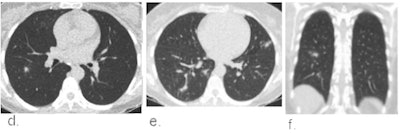

Schalekamp's team sought to evaluate the efficacy of using the CO-RADS system for chest CT in patients with moderate to severe symptoms of COVID-19. The system scores pulmonary involvement using a scale of 1 to 5 (1 = normal, 5 = typical for COVID-19). A score of 4 or higher is considered highly indicative of COVID-19.

The study included 1,070 patients who presented in the emergency departments of six Dutch medical centers between March and April. Chest CT exams were scored using CO-RADS and the scores compared with RT-PCR results and a clinical reference standard that included factors such as COVID-19 contact history, oxygen therapy, and the timing of RT-PCR testing. The investigators rated CT's performance using receiver operating characteristics curve (AUC) analysis and odds ratios; they also considered the timing of patients' symptoms (from less than 48 hours to more than seven days).

The CO-RADS system showed comparable diagnostic performance to RT-PCR testing and the clinical reference standard, especially after patients had symptoms for 48 hours or more.